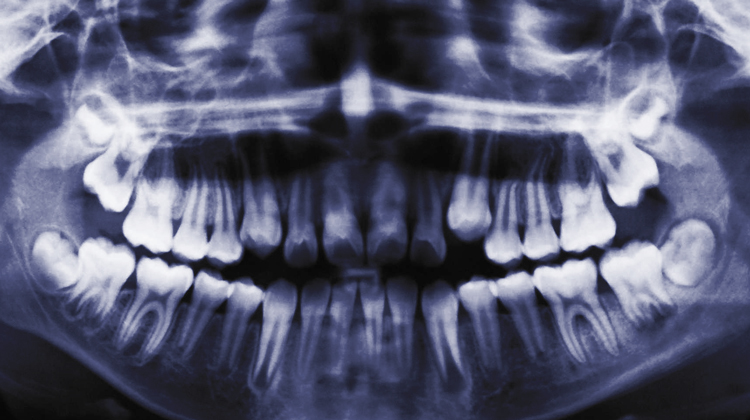

La radiografía digital debido a sus múltiples ventajas está tomando cada día mayor auge en el diagnóstico odontológico sin embargo ha de diferenciarse entre lo que es una radiografía digital y una radiografía digitalizada, ya que la calidad de imagen entre ellas puede variar sensiblemente, son realmente muchas las ventajas que involucran el éxito de la radiografía digital, sin embargo la comunidad odontológica toma sus precauciones respecto a su utilización como prueba clínica en la investigación experimental y su utilización como documento legal.